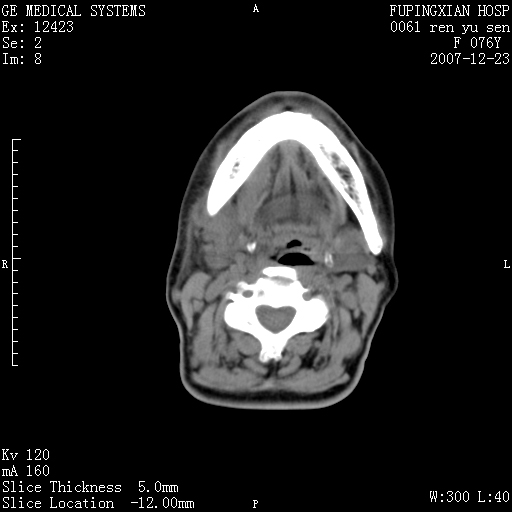

男性 76岁 下颌右侧磨牙区肿物数月, 约2.0*1.5cm大小波及颊舌侧,伴颌下淋巴结肿大。余(-)

右颈部颌下腺前可见一类圆形软组织密度影,密度不均,内见小片坏死区.颌下颈前可见两枚肿大淋巴结影.考虑淋巴结感染可能性大,建议增强扫描..

右侧第四磨牙缺失,局部牙槽骨质破坏,边界欠清晰,同侧颌下及竟不见多发肿大淋巴结显示。考虑肿瘤病变可能性大,感染待排